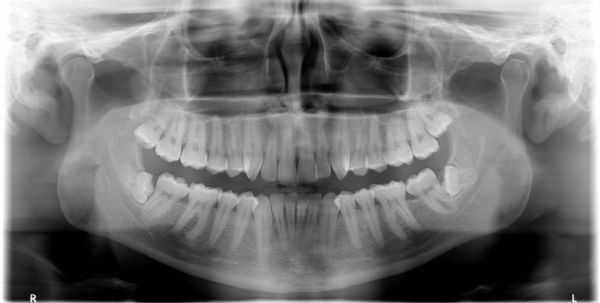

(Слева) На панорамной рентгенограмме у пациента с двухлоронним передним вывихом визуализируется правый мыщелок, смещенный кпереди и кверху относительно сулавного возвышения. Обратите внимание на явный передний открытый прикус, в то время как моляры находятся в окклюзии.

(Справа) На панорамной рентгенограмме у этого же пациента определяются аналогичные изменения слева. Открытый прикус обусловлен неправильным передним положением мыщелка, контакт задних зубов - его верхним положением.

2. Рентгенография при вывихе височно-нижнечелюстного сустава (ВНЧС):

• Радиографические признаки:

о Передне-верхнее положение мыщелков по отношению к суставному возвышению

о Панорамная рентгенография для первоначальной оценки

о КТ в костном окне и КЛКТ с трехмерной реконструкцией для оценки анатомических отношений смещенного мыщелка